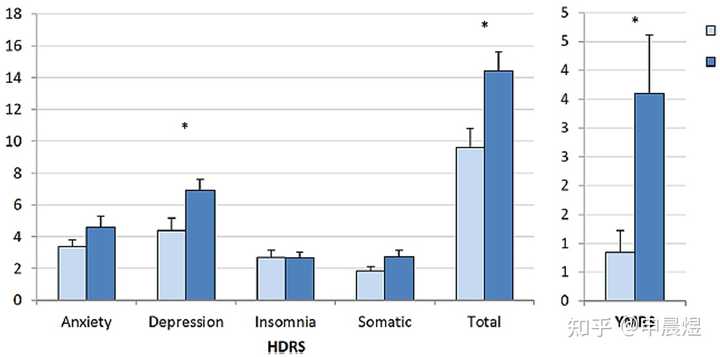

抑郁症可致生物节律相位延迟

抑郁患者的生物节律往往是相位延迟的,意味着早上觉醒度不足,晚上入睡困难。难以入睡进一步加剧了白天的困倦感[7]。

抑郁症患者的睡眠结构节律紊乱[8]